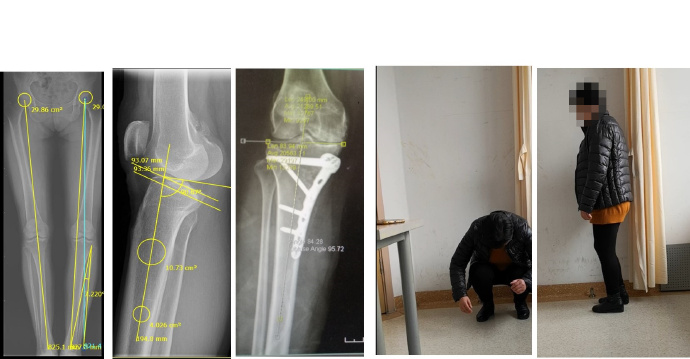

陈旧胫骨平台畸形愈合矫正

男,47岁,因外伤致左膝关节骨折术后4月,伴左膝畸形,行走障碍入院。

病例:陈旧平台骨折

外观:明显内翻畸形;旋转畸形不明显

原始影像资料:

Schatzker 分型为V型:双髁骨折,伴不同程度的关节面塌陷和移位

膝关节的骨折脱位型,1981。